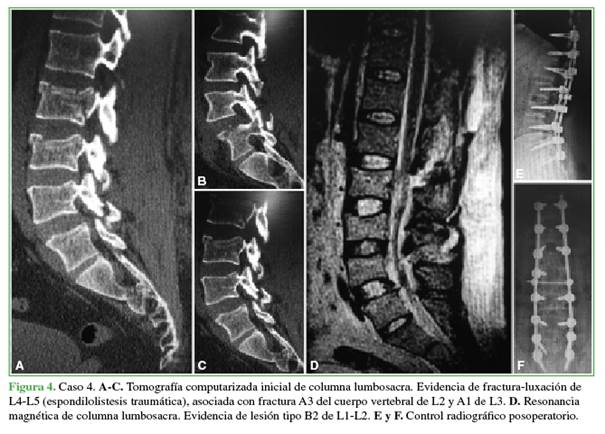

Durante el período de estudio, hubo cinco pacientes (1 mujer y 4 hombres) con dos fracturas vertebrales inestables simultáneas, con cuatro casos (80%) de fracturas no contiguas. De acuerdo con el tipo de fracturas asociadas, tres (60%) tenían dos luxofracturas (AOSpine: tipo C) simultáneas no contiguas, asociación denominada columna flotante, según publicaciones previas. Como variante de lesión, dos (40%) pacientes tenían la asociación de una fractura tipo B con una tipo C. La mediana de la edad era de 35 años (rango 23-49). Todos habían sufrido traumatismos de alta energía (3 accidentes de tránsito, 2 caídas de gran altura) con lesiones asociadas. Predominó el traumatismo grave de tórax con fracturas costales y hemotórax (n = 3, 60%). Se registraron escasas comorbilidades previas: un paciente con antecedente de depresión mayor e intento autolítico y uno con osificación del ligamento longitudinal posterior cervical. En la Tabla 1, se resume la descripción de la muestra y, en la Tabla 2, se describen los casos (Figuras 1-4).